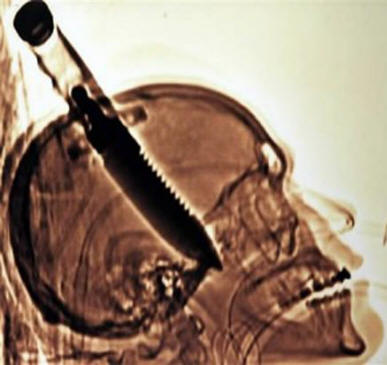

1998-ban Michael Hill egy barátjával ellátogatott Floridaba, amikor hirtelen az utcán egy őrült felrohant hozzá és … ok nélkül minden ok nélkül megragadta egy csupasz késbe. Maga Michael hazajött, igaz egy fogantyúval, amely kilóg a fejemből, és csak ott sokkolta egy barátja mentőt hívott. Hill később ezt mondta szinte nem érezte a fájdalmat a fejben (bár a tomográfia azt mutatta a kés kb. 20 cm-rel behatolt az agyba!), az egyetlen megjegyezte, hogy ez “hő a jobb szemben”. Négy órás műtét után Michael már áthelyezték az egyházközségbe, és néhány nappal később lemerült. Végül a srác bal karja megbénult, de az orvosok szerint még mindig könnyen elszállt.